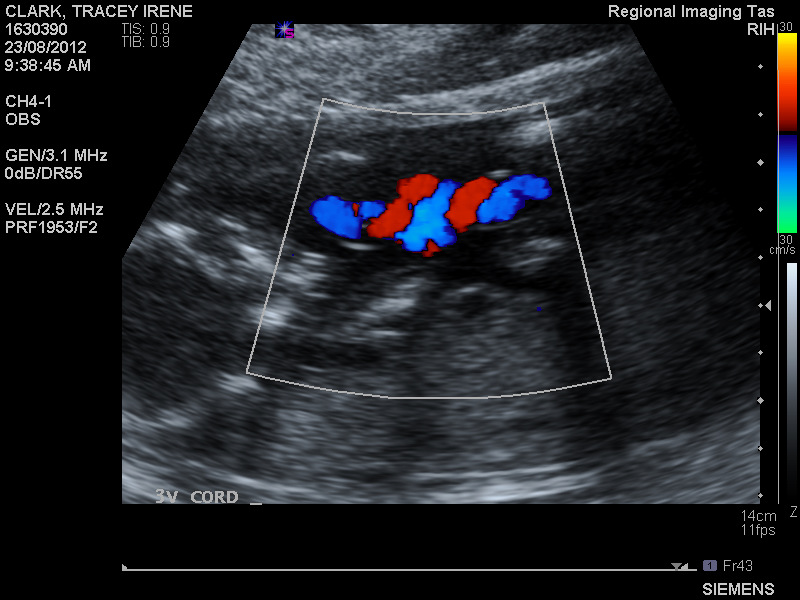

We managed to get a really good sonographer this time who talked to us the whole time, explaining every little detail that he was seeing. He agrees with me that Drew most likely was born with a two vessel cord seeing as he had so many problems, and so the first thing he checked was the cord:

Perfect. The cord has three vessels at each end and is attached nicely at both ends too. So that eliminates my biggest worry of all, because all of the issues that found with Sophie came from the cord. After that I was pretty relaxed really and just enjoyed the ride.